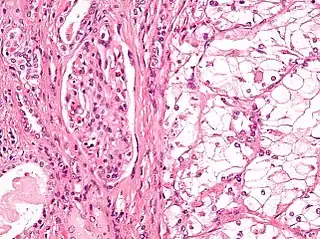

![]() Micrografía que muestra el tipo más común de cáncer de riñón (carcinoma de células renales de células claras). Tinción H&E. | ||

El tipo más común de malignidad renal es el carcinoma de células renales,[33] que se cree que se origina en las células del túbulo contorneado proximal de la nefrona.[15][34] Otro tipo de cáncer de riñón aunque menos común, es el cáncer de células de transición (CCT) o carcinoma urotelial de la pelvis renal.[35] La pelvis renal es la parte del riñón que recoge la orina y la drena en un tubo llamado uréter.[35] Las células que recubren la pelvis renal se denominan células de transición y, a veces, también se denominan células uroteliales. Las células de transición/uroteliales en la pelvis renal son el mismo tipo de células que recubren el uréter y la vejiga. Por esta razón, el CCT de la pelvis renal es distinto del CCR y se cree que se comporta más como el cáncer de vejiga.[35] Otros tipos raros de cáncer de riñón que pueden surgir de las células uroteliales de la pelvis renal son el carcinoma de células escamosas y el adenocarcinoma.[15]

El carcinoma de células renales se ha dividido en subtipos según las características histológicas y las anomalías genéticas. La clasificación de la OMS de 2004 de los tumores renales de los adultos describe estas categorías:[39]

- CCR de celda clara